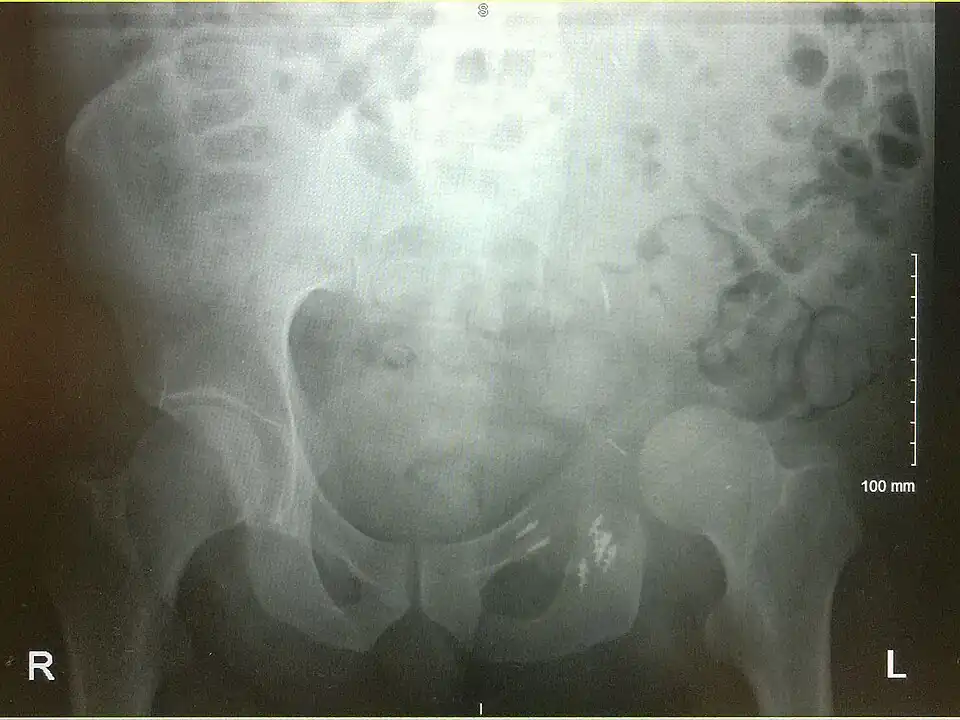

An x-ray of the same pelvis taken eighteen months after surgery highlighting the femur migration to its final resting place.